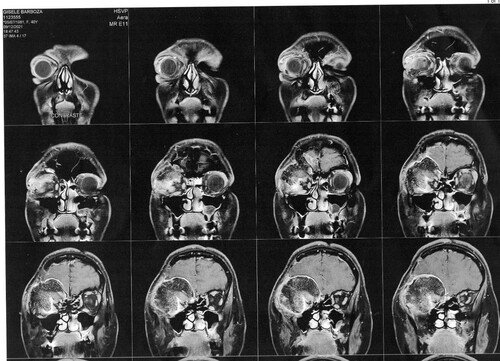

1 ano e 7 meses após o nascimento da Manuela (hoje com quase 4 anos), mais precisamente em dezembro de 2018, Gisele foi em busca de um neurocirurgião que estivesse apto a realizar a cirurgia. Optou-se por um médico da região, pela facilidade de locomoção. Por sua vez, por meio de exames de imagem, este médico a diagnosticou com um meningioma intraósseo (tumor cerebral benigno que se origina nas células das meninges).

Então este médico solicitou exames de imagem (ressonância magnética e tomografia) para avaliar a situação, os quais foi constatado que o meningioma ainda está ali, e que continua empurrando o olho e se expandindo para outras áreas. Trata-se de um meningioma gigante (medindo 6 x 6,6 x 6 cm), que está localizado na placa do assoalho da fossa média e anterior.